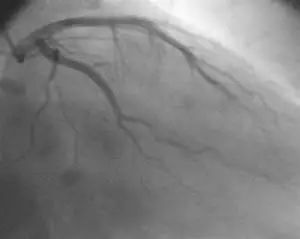

06

左主干冠心病的最佳治疗策略